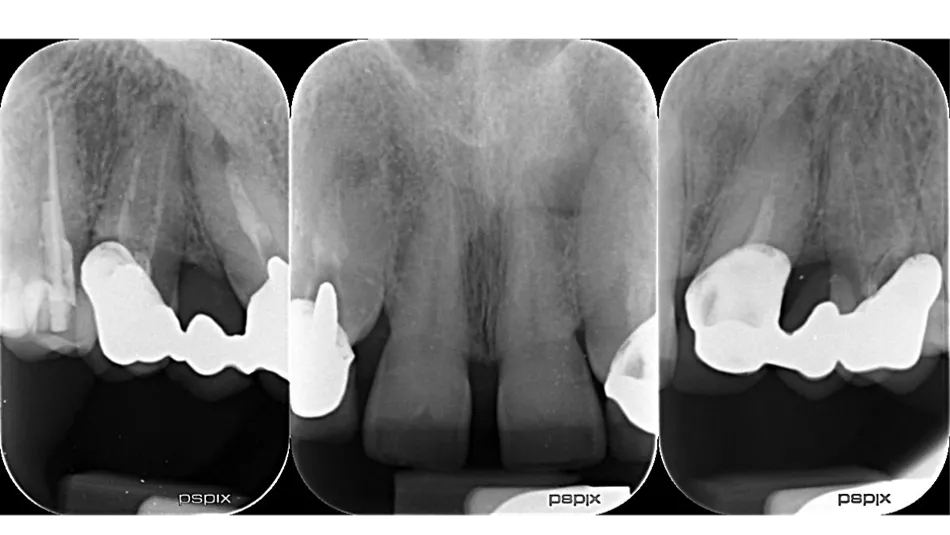

2a-b-c. Initial X-rays. The cause of the endodontic lesions was obvious, and they are underestimated on these retro-alveolar X-rays.